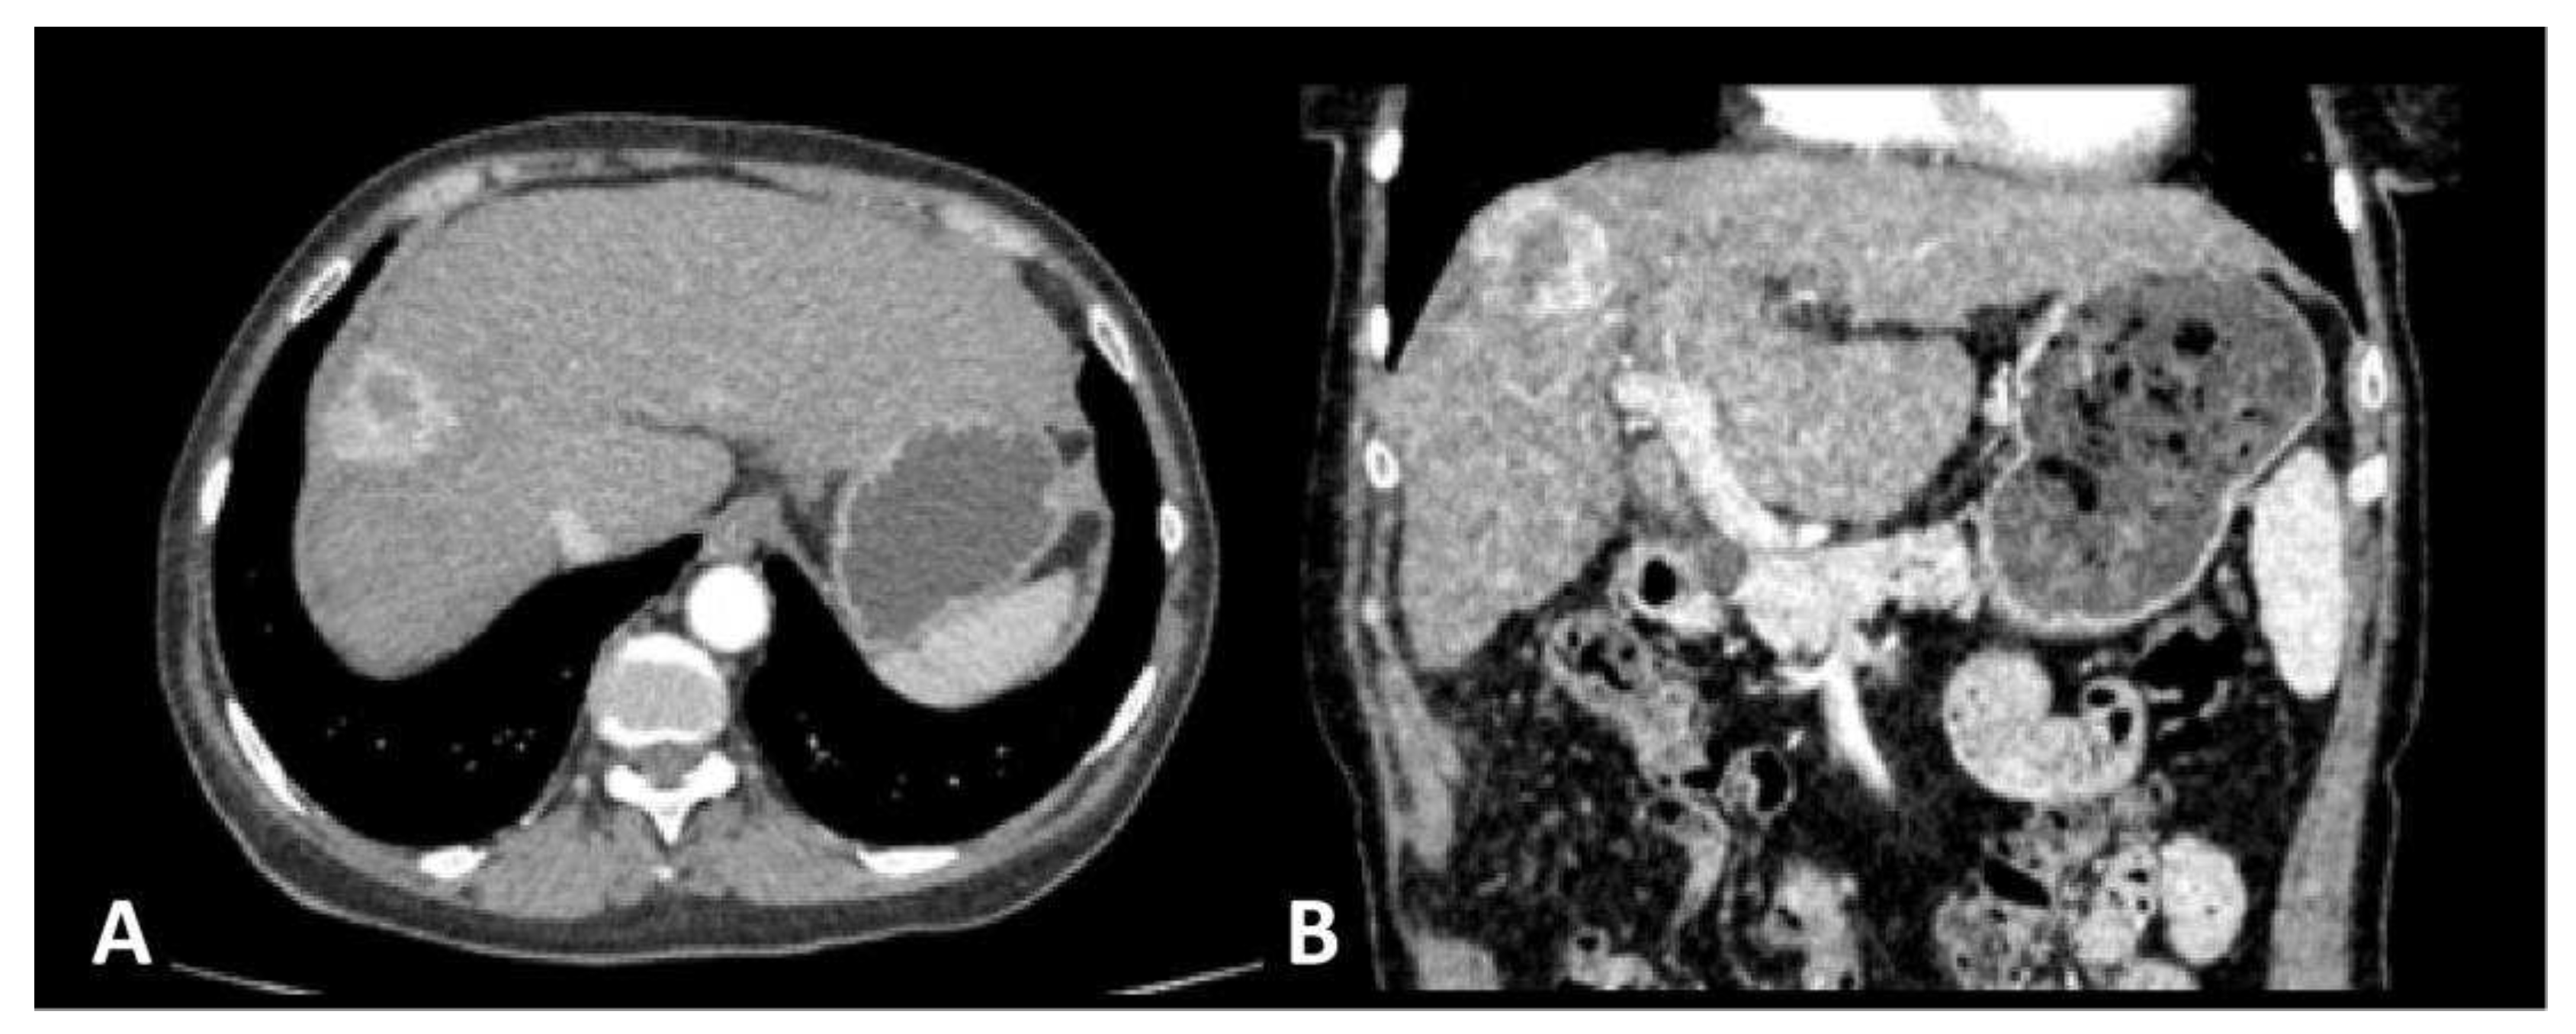

A 65-year old female patient was admitted to the surgical clinic with previously detected Computed Tomography (CT) presentation of a subcapsular 3 cm solitary, hyper vascular, primary liver tumor in the segment VIII, in the setting of a cirrhotic liver caused by chronic HCV infection, highly suggestive of an HCC (Figure 1). The CT scan demonstrated signs of portal hypertension, such as recanalization of paraumbilical veins, discrete venous collaterals in the omentum and esophageal varices. Additionally, there was no evidence of extrahepatic disease in the thorax, abdomen or pelvis, nor signs of ascites. Upon admission to the hospital and detailed clinical and laboratory work-up, the patient was classified as Child-Pugh class A, with the following values: total bilirubin level of 20.2 mmol/L, albumin level of 39 g/L, INR of 1.16, without signs of ascites or encephalopathy. Furthermore, the patient’s performance status, assessed by the Eastern Cooperative Oncology Group (ECOG) grading system, was 0. Considering the patients favorable performance status, without comorbidities, and Child Pugh class A, the patient met the stage A criteria by the Barcelona Clinic Liver Cancer (BCLC) and curative-intent surgical intervention (open anatomic resection of liver segment VIII) was performed. The pathohistological (PH) report of the resected specimen confirmed the presence of a moderately differentiated G2 trabecular-type HCC, pathological Tumor-Node-Metastasis (pTNM) staging of IB, with no residues of the tumor on the surgical margin – R0 resection. The postoperative course was uneventful and the patient was discharged from hospital on postoperative day 7. The first follow-up visit was scheduled for one month and further more on 6 months basis. Given the curative R0 resection, no chemo- or radiotherapy was advised.

Figure 1. Axial (a) and sagittal (b) images of a contrast-enhanced CT scan obtained in the arterial phase reveal the presence of a solitary, hyper vascular, liver tumor in the segment VIII of the liver, with washout in portal-venous phase (not shown in these images), consistent with the radiological features of an HCC in the setting of a cirrhotic liver.